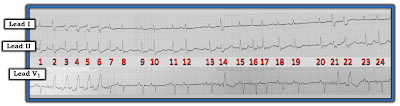

| Figure-1: ECG obtained from an elderly woman awaiting surgery. |

- PEARL #1: In addition to using a systematic approach and using calipers — I find it extremely helpful to look for an underlying rhythm. Simply stated — when there is more than one active feature in the rhythm — LOOK FIRST for the EASIER elements to interpret. Save the more difficult elements for later. For example, in Figure-1 — I would save the run of wider, faster beats (ie, beats #2-thru-6) until after I’ve assessed other parts of this tracing that look to be easier to interpret.

- Ignoring the wider beats for the time being (as per Pearl #1) — the QRS in all 3 leads is narrow for the remaining beats ( = beats #1; 7-13; 15-20; and 23, 24). Therefore — the underlying rhythm is supraventricular.

- This underlying rhythm for these narrow beats is not Regular. As a result, the Rate varies — but a tachycardia is present, as the R-R interval is virtually always less than 3 large boxes in duration (ie, the average rate is clearly over 100/minute).

- P waves are present — and they do appear to be Related to neighboring QRS complexes, in that a P wave precedes virtually all QRS complexes.

- PEARL #2: P wave morphology appears to be changing, almost from beat-to-beat thoughout the entire rhythm strip in Figure-1. This constantly changing P wave morphology is subtle-but-real, although not easy to appreciate from lead V1 — because most P waves in this lead are pointed. The KEYS to appreciating the variation in P wave morphology are to: i) Note that the PR interval does not remain the same; and, ii) Look at P waves in each of the simultaneously-recorded leads. For example, although the P wave preceding beats #11, 12 and 13 in lead V1 is pointed at its peak — the change in morphology from one P wave to the next preceding these same beats #11, 12 and 13 is much more obvious in simultaneously-recorded leads I and II.

- Looking closely — the P waves preceding beats #14, 21 and 24 in lead V1 appear to be biphasic. While true that it sometimes is difficult to distinguish between variations in P wave morphology that result from baseline artifact or the "normal" variation in shape than can often be seen between one sinus P wave and the next — I interpreted the above described variation in P wave morphology as real.

- MAT is not a common diagnosis. As a result, in order to differentiate MAT from the much more commonly encountered irregularly irregular rhythm (which is AFib) — we need to be certain we are seeing multiple different P wave morphologies that are constantly changing. Pearl #2 above describes how we are!

- The first wide beat in each of the 3 places where wide beats occur on the long lead rhythm strip is clearly preceded by a premature P wave (RED arrows before beats #2, 14 and 21 in Figure-2).

- P waves also precede the other wide beats on this rhythm strip (PINK arrows before beats #3, 4, 5, 6 and 22).

- Each of the widened beats in Figure-2 manifest a RBBB (Right Bundle Branch Block) morphology, with upright widened QRS in lead V1 and wide, terminal S wave in lateral lead I. The first wide beat in each grouping (ie, beats #2, 14 and 21) manifests the highly specific triphasic rsR' pattern that is so characteristic of aberrant conduction (See Video Pearl MP-28 below in the Addendum for full explanation why RBBB morphology is the most common pattern with aberrant conduction).

- PEARL #5: The Ashman Phenomenon is present, and explains why beats #14, 21 and 22 conduct with RBBB aberration. As explained in detail in Audio Pearl MP-29 near the top of this page — the preceding R-R interval is proportional to the length of the subsequent relative refractory period. As a result — aberrantly-conducted beats often follow the longest pauses in a rhythm strip (ie, The longest pauses in Figure-2 = the R-R intervals between beats #12-13, and between beats #19-20).

- Beyond-the-Core: Did YOU notice that in addition to the typical RBBB morphology for the widened beats — that a typical hemiblock morphology is also present for most of the widened beats? Specifically — the deep S wave descent in lead I for beats #3, 4, 5 and 6 is characteristic of LPHB (Left Posterior HemiBlock) conduction — and predominant negativity of the QRS in lead II for beats #14 and 21 is characteristic of LAHB (Left Anterior HemiBlock) conduction. The presence of this alternating typical pattern of bifascicular block conduction (RBBB/LPHB and RBBB/LAHB) provides yet one more finding in strong support of aberrant conduction.

- As emphasized above in Pearl #3 — the success in treating MAT depends on identifying and correcting the underlying cause of this rhythm. Awareness that the elderly patient in today's case had both hypokalemia and hypoxemia explains why treatment with several antiarrhythmic agents failed to control her arrhythmia.

- In addition to the underlying rhythm of MAT — the rapid succession of PACs at the beginning of this rhythm strip (ie, beats #1-thru-6) constitues a run of Atrial Tachycardia, in which beats #2-thru-6 are wide because of aberrant conduction. There is no evidence of VT on this tracing. Hopefully, correction of the electrolyte disturbance and the patient's hypoxemia will help to resolve both the MAT and the runs of Atrial Tachycardia.